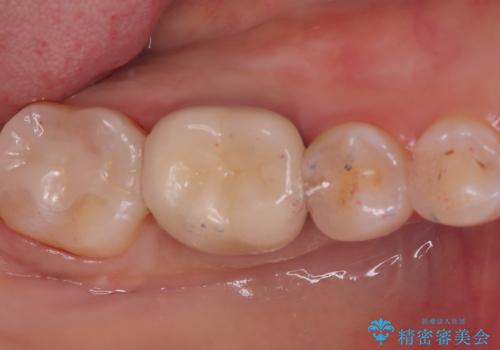

クリーニングにいらした患者さんで、右下7番目の歯の奥側の面や手前の歯との間にう蝕があり、噛む面にも蝕処置によるレジン材料が詰まっていたことから、う蝕も古い材料も全て除去しセラミックインレーでのやり替えとなりました。

右下7近遠心にカリエスを認め、咬合面のCR修復も劣化していたので、カリエスと古い材料を全て除去し新しくCR裏層した後、セラミックインレーをセットしています。セット時はラバーダム防湿を行っています。